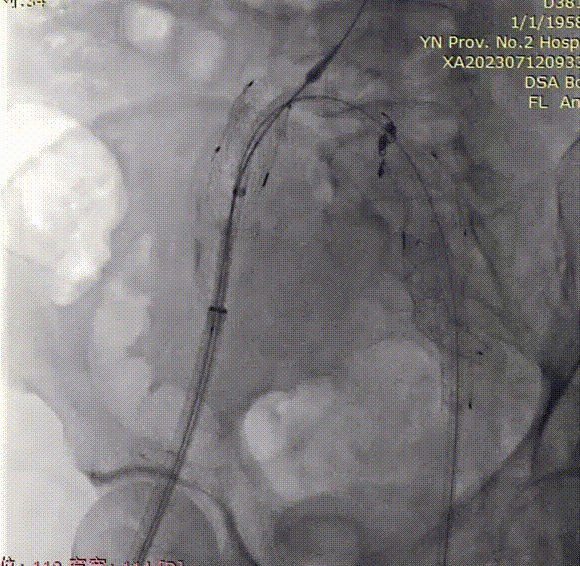

最后造影

支架锚定位置如预期,隔绝良好,无明显内漏;双侧髂内动脉血供得以保留,血流通畅。